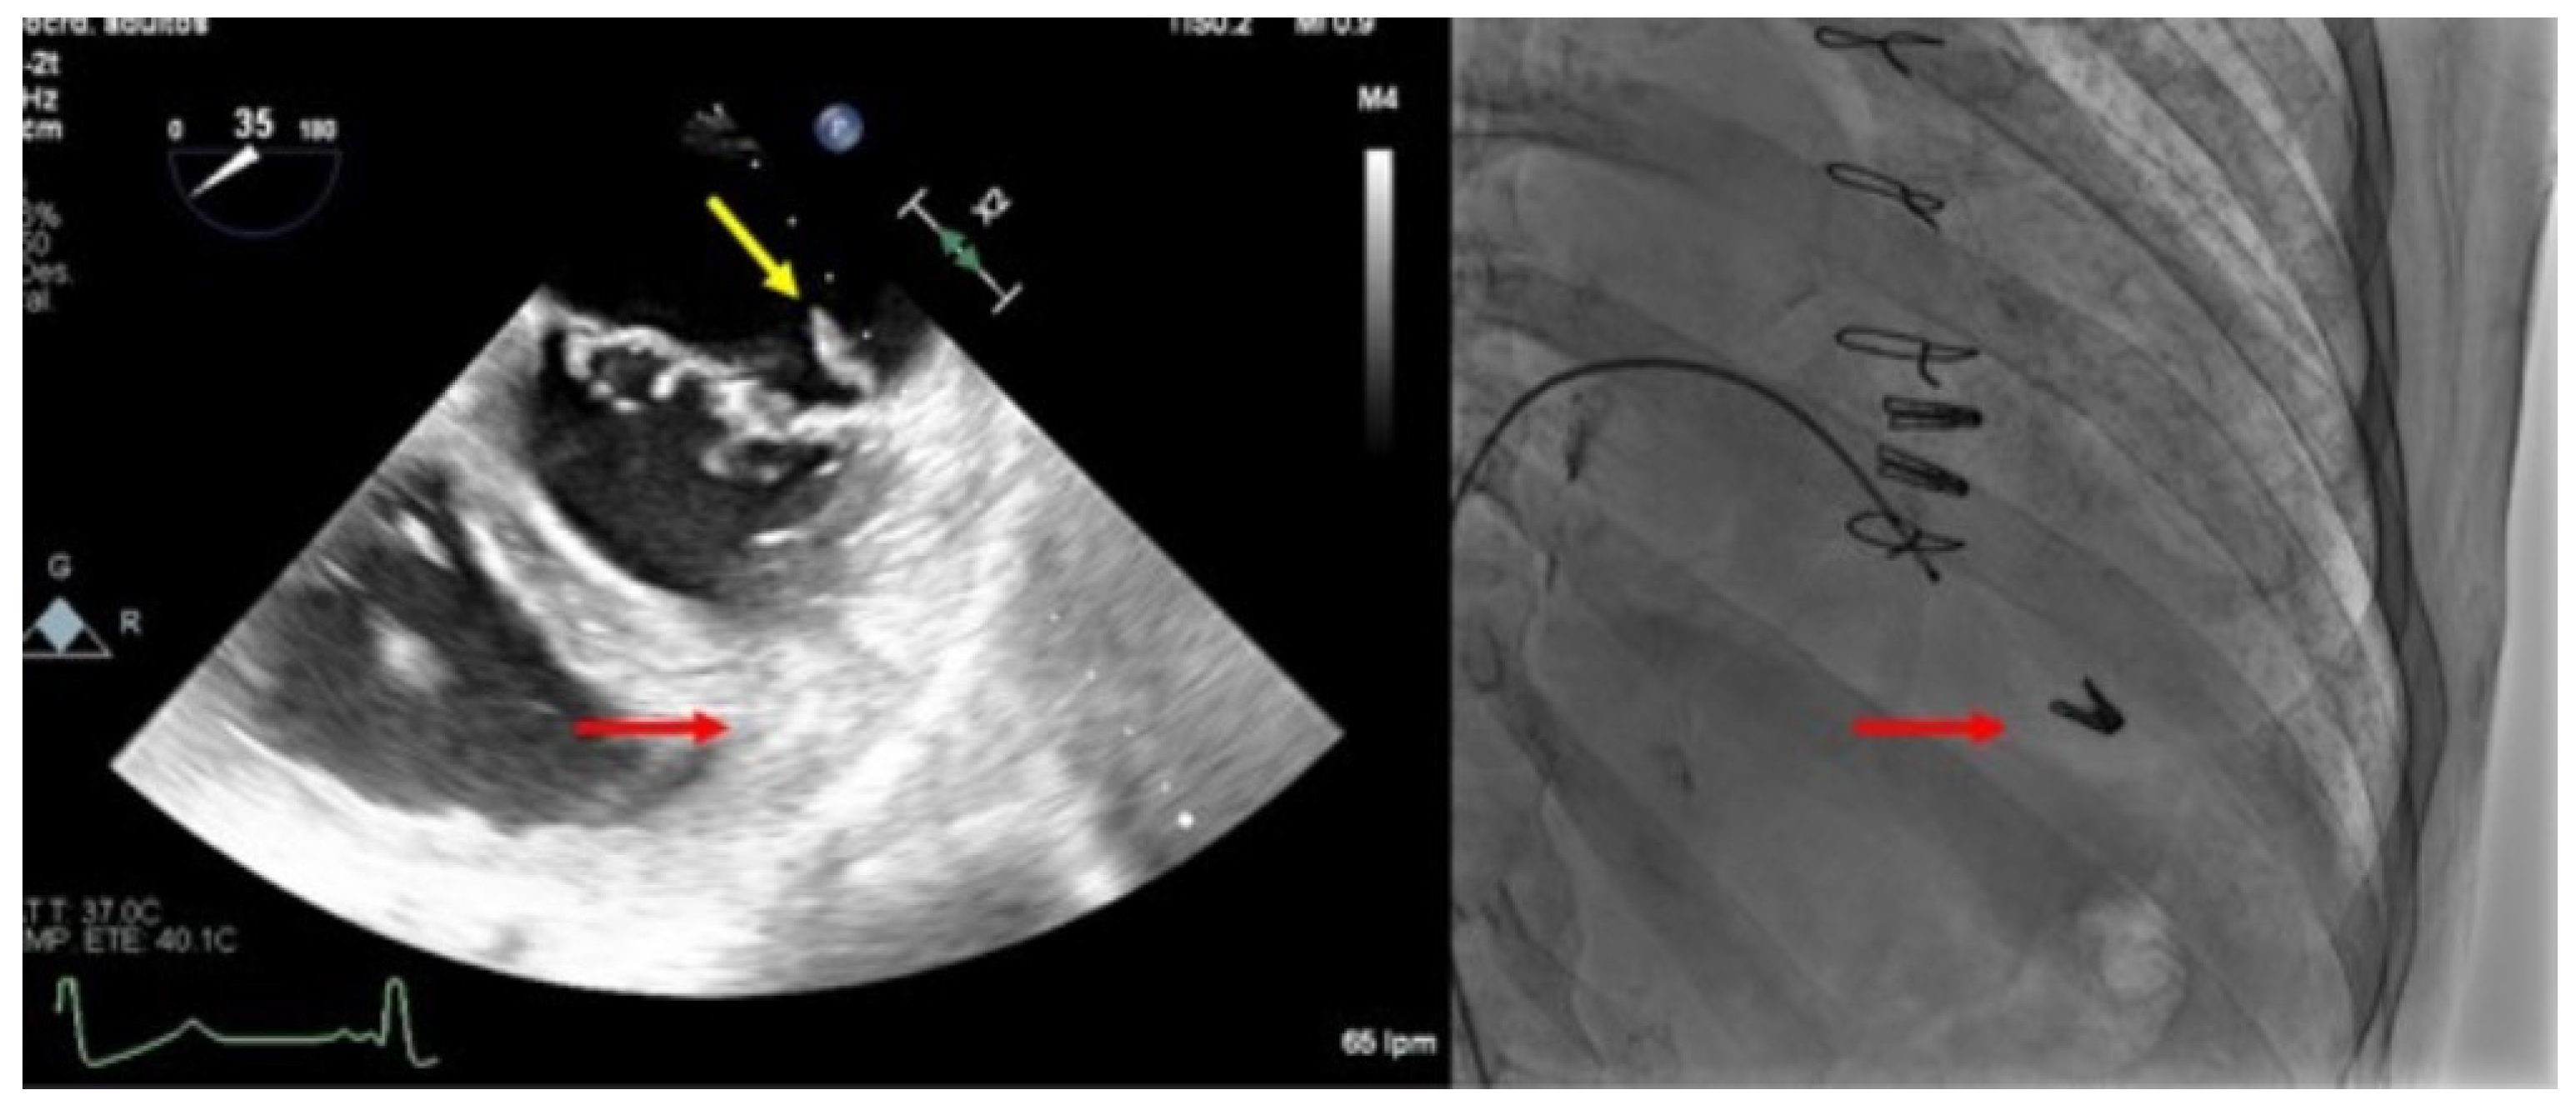

Complex mitral anatomy and several-clips implantation with suboptimal echocardiographic window due to the artefacts of the other clips, may be associated with clip embolization (Figure 6). Meticulous intra-procedural imaging with a clear visualization of the device, leaflets, and subvalvular apparatus reduces the risk of detachment.

Figure 6.

Clip embolization. (Left) Two-dimensional transesophageal echocardiogram showing a posterior leaflet prolapse (yellow arrow) after retrograde embolization of a clip to the right ventricle through the procedural atrial septal defect (red arrow). (Right) Fluoroscopy image at the end of the procedure showing two clips implanted in the mitral valve and another one embolized in the apex of the right ventricle (red arrow).